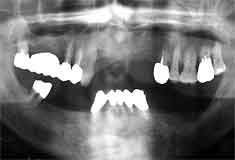

初診時 パノラマ 10年後 パノラマ

歯槽骨吸収は約1/2 将来が危ぶまれる状況

40歳・女性

10年間骨吸収はほとんど停止、喪失歯もなく経過良好

口腔清掃状態はそれ程悪くはないが、全体に歯槽骨吸収が著しく、軽度なところで1/3以上、 著明なところは1/2以上吸収しており、40歳という年齢を考えると将来は悲観的。

75|は抜髄の上、歯周外科処置(FOp+HAP)を行い、それ以外の部位については、 P-cur と毎月のプロフェッショナル・トゥースクリーニングを行い経過観察することとした。 初診より5年を経過した頃より|6の知覚過敏を訴えるようになり、薬物塗布により鎮静 に努めたが、最終的には歯髄壊疽により根管治療を行った。

治療の時に悲観的だった7|6は、それぞれ動揺と軽度な咬合痛が消失しないまま 長期にわたり機能し続けている。

一方着目すべきは、それ以外の歯が10年後も初診時と変わらず、あたかも骨吸収進行が停止 したかのように思える点である。

初診時(40歳)までの歯槽骨吸収速度と、メインテナンスを始めてから10年間の進行速度が 明らかに違う。P-cur と毎月のプロフェッショナル・トゥースクリーニングだけで獲得できた意義 は臨床家として高く評価したい。